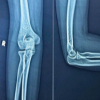

Postoperatively, the patient participated in outpatient physical therapy 2–3 times per week for 9 weeks, beginning 4-day postoperatively. During physical therapy, a decline in peak ROM was noted at 4 weeks. X-rays taken at this time confirmed proper joint alignment and well-affixed implants (Fig. 1, Top Right). The patient’s medical history includes high cholesterol and sleep apnea, as well as hearing loss and frequent urination. The patient was a former smoker, who ceased over 16 years ago and self-reports a moderate level of alcohol consumption. Preoperatively, the patient had a limited peak ROM of 5–95°. During the first 2 weeks following surgery, the patient averaged a functional ROM of 42°. The recovery curve for this parameter shows that the patient was below the 25th percentile, among men ≥65 years. Peak ROM was 4–83° at 2-weeks post-TKA. Functional ROM averaged 43.5° over weeks 3 and 4, followed by a decrease at week 5, illustrated on the recovery curve as the patient’s functional ROM falling below the 5th percentile. 7-week post-TKA, the peak ROM had increased to 3-115° but the functional ROM was only at the 10th percentile. Although the patient had made progress in their peak knee flexion, they were still unable to reach full extension of the knee, and the patient reported increased pain and swelling. For these reasons, an MUA was performed 9 weeks following surgery. Following the MUA, physical therapy was prescribed 5 times per week for 2 weeks, followed by an additional 2–3 times per week for 6 weeks. Three weeks following MUA, functional ROM increased to an average of 48.5°, while peak ROM was 11–99°. By 7-week post-MUA, approximately 16 weeks after initial TKA, the patient had a functional ROM of 50.3°, and peak ROM was measured at 6–111°. Over the next 4 weeks, the patient averaged 52° of functional ROM (Fig. 2, Top). Patient two is a 34-year-old female who underwent a primary left TKA on June 1, 2022 with no complications. Pre-operative X-rays confirmed severe osteoarthritis and joint space narrowing (Fig. 1, Middle Left). The patient participated in outpatient physical therapy 1–3 times per week for 6 weeks starting 2 days after surgery. Post-operative X-rays confirmed proper joint alignment and well-affixed implants (Fig. 1, Middle Right). The patient’s past medical history consists of a previous ACL and meniscal repair, hypothyroidism, arthritis, and Type 2 diabetes. This patient does not have a history of smoking and self-reports occasional alcohol consumption.

Preoperatively, the patient had a limited peak ROM of 19–71°. During the initial 2 weeks following surgery, the patient averaged only 37° of functional ROM, below the 5th percentile among females ≤65 years (Fig 2, middle). At her 2-week follow-up, the patient’s peak ROM was 17–70°. The functional ROM average between weeks 3 and 6 was 43.75°. At 6 weeks post-TKA the patient’s peak ROM had only improved to 3–86°. The patient underwent MUA at 7-week post-TKA due to arthrofibrosis limiting knee mobility. Following MUA, physical therapy was prescribed 1–3 times per week for 6 weeks. Over the 2 weeks following MUA, the patient averaged 49° of functional ROM and had an improved peak ROM of 6–91°. At 5-week post-MUA, the patient had a peak ROM of 0–107°, and was averaging 51° of functional ROM. The patient continued to be remotely monitored and showed continuous improvements in functional ROM with an average of 54° between 16- and 20-week post-TKA (Fig. 2, Middle). Patient three is a 51-year-old female who underwent primary left TKA on June 1, 2022 with no complications. Pre-operative X-rays confirmed severe osteoarthritis and joint space narrowing (Fig. 1, Bottom Left). The patient began outpatient physical therapy 2 days after surgery and continued 2–3 times per week for 6 weeks. Post-operative X-rays confirmed proper joint alignment and well-affixed implants (Fig. 1, Bottom Right). This patient’s medical history consists of previous left knee ACL reconstruction, knee arthroscopy with partial medial and lateral meniscectomies. This patient does not have a history of smoking and self-reports occasional alcohol consumption. Preoperatively, the patient had a limited peak knee ROM of 13–102°. During the 2 weeks between surgery and the initial clinical visit, the patient averaged 51.5° of functional ROM. At her 2-week follow-up, the patient had a peak ROM of 0–105°. Over the following 4 weeks, the patient averaged 57.8° of functional ROM and had a peak ROM of 0–124°. From week 8 through 20 post-TKA, this patient maintained a relatively stable functional ROM, averaging 63.6° throughout this time period (Fig. 2, Bottom).